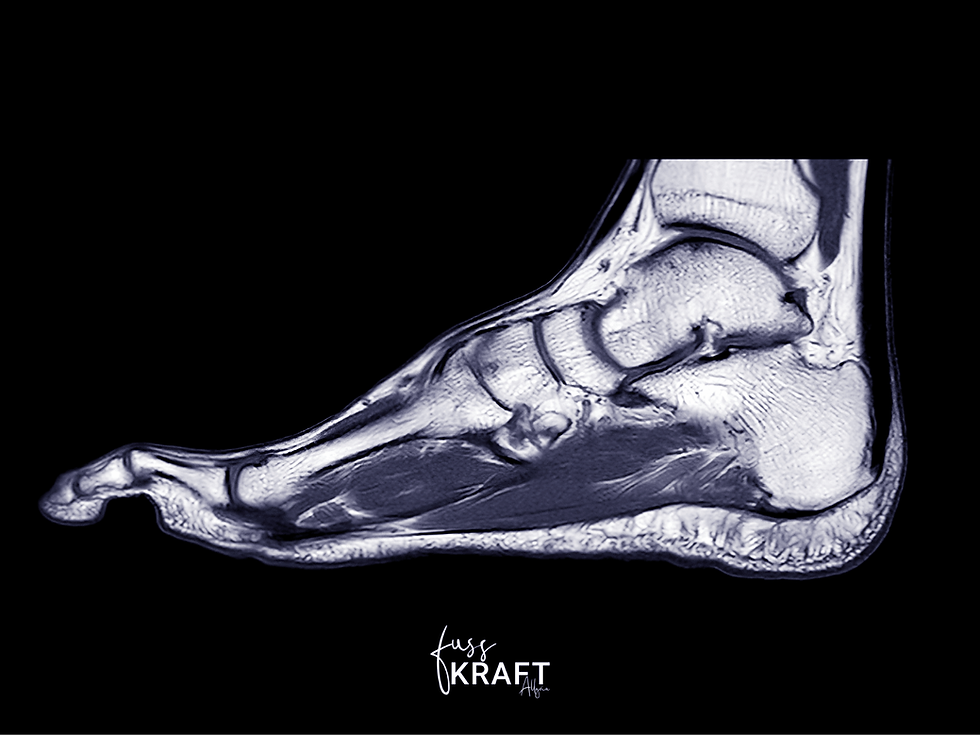

Hast du dich jemals gefragt, wie viel Kraft tatsächlich in deinen Füßen steckt? Ein MRT-Bild eines menschlichen Fußes zeigt eindrucksvoll, wie viel Raum die Muskulatur in der Fußsohle einnimmt. Das könnte ein Beweis dafür sein, dass unsere Füße keineswegs schwach sein müssen, sondern erstaunlich muskulös, leistungsfähig und kräftig sein können.